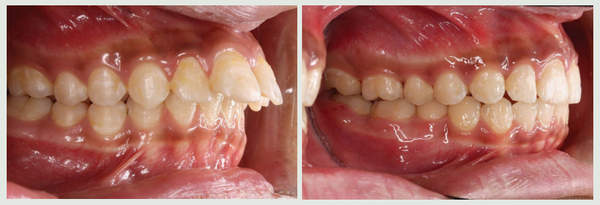

가톨릭대학교 서울성모병원 치과병원 국윤아 교수(교신저자)와 주홍국 원장(맨해 튼치과, 제1저자) 연구팀이 부정교합 환자를 대상으로 치아를 발치하지 않고 후방 이 동하는 교정법을 적용해 3년간 장기 관찰한 결과 치열을 후방이동시켜도 기도공간 에는 문제가 없음을 최초로 규명해 MCPP(Modified C-palatal plate)를 이용한 비발치 교정법의 안정성을 다시금 입증했다.

MCPP 치료군은 기도공간에 있어 치료 후 유지기간 동안 유의할만한 변화량을 보이지 않았으며 대조군과도 차이가 없었다.

연구결과는 2급 부정교합을 가진 청소년 환자에서 MCPP 교정치료가 기도공간 및 골격적으로 부정적인 영향을 미치지 않는 효과적인 치료방법임을 시사했다. 특히 교 정치료로 인해 치열이 뒤로 밀리면 기도가 좁아지지 않을까 우려하기 쉬운데 골격적 이상이 없다는 점이 입증돼 기도 공간이 좁아질 때 생길 수 있는 수면무호흡증과도 무관하다는 점이 주목할 만하다.

과거 헤드기어와 같이 구외(口外) 장치를 착용해 치료하던 것과 달리 특수하게 고 안된 골격성 고정장치를 입천장에 고정해 심미적으로 효과가 있고 불편감을 최소화하며 어금니와 전체 치열을 치아 뒤쪽 방향으로 이동시키게 된다.

발치를 하지 않기 때문에 자연치아를 보존할 수 있다는 점이 큰 장점이다. 또한 골 격적 부조화가 심해 수술이 필요한 환자가 MCPP를 사용해 비수술 교정치료를 할 수 있고 치열에 공간이 부족해 치아가 매복돼 있는 환자도 치열을 후방 이동함으로써 공간을 확보해 매복된 치아를 살려서 사용할 수 있다.